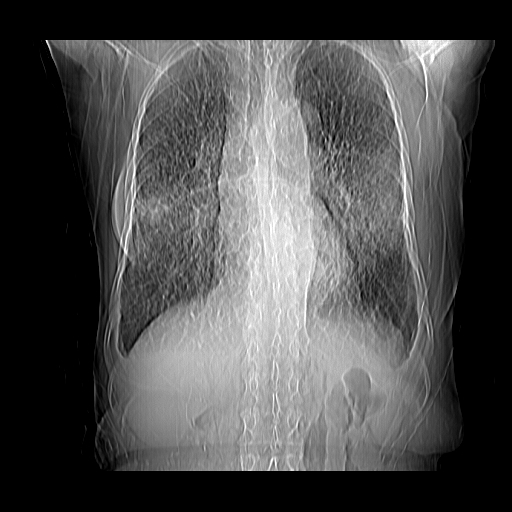

女70y乳腺ca(针吸活检)

多部位转移瘤的诊断可以肯定,我的疑问是:双肺对称高密度影及胸水是否为心衰肺水肿,病人体虚弱,不好意思图象传的乱![em9]

1)左侧乳腺癌并左侧腋窝及纵隔淋巴结转移,两肺淋巴道转移(癌性淋巴管炎),肝脏多发性转移。2)双侧胸腔积液。3)慢性胆囊炎。

1)左侧乳腺癌并左侧腋窝及纵隔淋巴结转移,肝脏多发性转移。2)双侧胸腔积液伴双肺蝶翼样磨玻璃高密度影,双侧肺门血管影增粗(图像不全,肺门层面没纵隔窗),考虑心功能不全所致。3)慢性胆囊炎伴壁钙化。